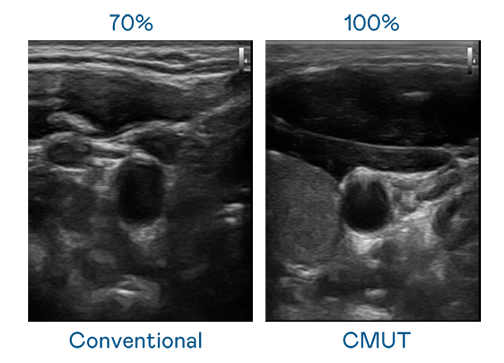

CMUT 技术是一种用电容式微机电元件来产生超音波讯号的技术。与传统 PZT 压电式技术相比,CMUT 频宽增加 30%,更宽频的超音波讯号让影像解析度大幅提升,是实现高影像品质医疗超音波扫描、促进精准医疗发展的关键技术。

大频宽带来超清晰影像

超音波影像的解析度高低,首先取决于探头能发出的讯号频宽。太阳成集团tyc151cc CMUT 可提供高清晰的超音波讯号,提供高频宽、高灵敏度、影像纹理细节更高的超音波影像,协助医护人员缩短影像判读时间及利用精准的医疗影像进行诊断。